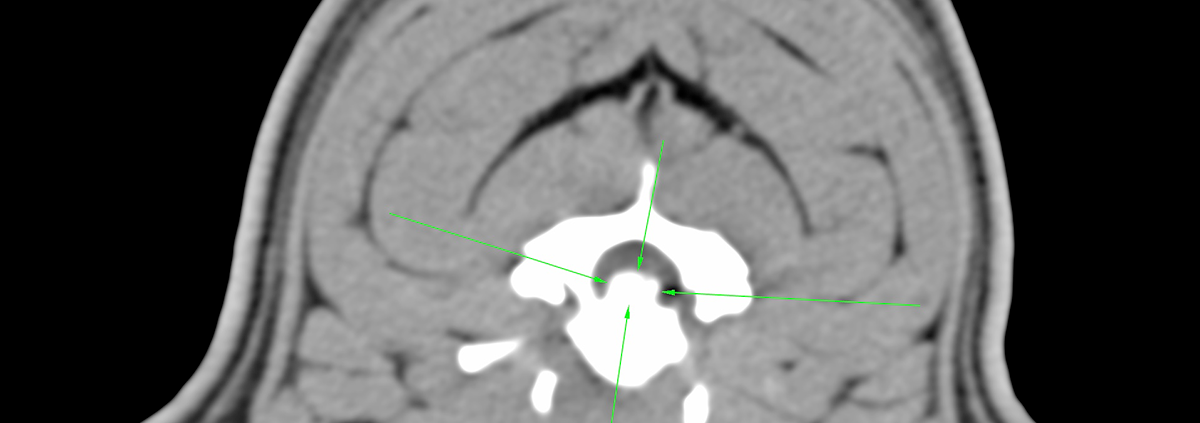

Tomografía computarizada. Se observa una hernia discal calcificada, migrada, central, sin lateralización aparente.

La tomografía computerizada (TAC)se utiliza para revelar el alcance del daño producido por la hernia discal y ayudar a planificar la cirugía. En casos muy leves de hernia discal, se puede intentar el tratamiento médico con relajantes musculares, analgésicos o esteroides orales. Aunque esto a menudo falla.